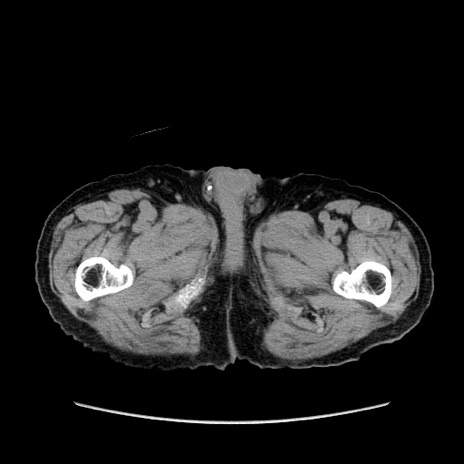

症例24(横断像)

【症例】80歳代男性

【主訴】左側腹部痛、嘔吐

【現病歴】本日早朝より左腹部に痛みあり。昼頃嘔吐認めたため、救急要請。

【既往歴】直腸癌(Mile手術)、胆摘

【身体所見】意識清明、BT 35.9℃、BP 221/93mmHg、SpO2 97%(RA) 、腹部:左ストーマ周囲に限局性の腹部膨隆あり。 膨隆部自発痛・圧痛あり・軟。

【データ】WBC 7700、CRP 0.09